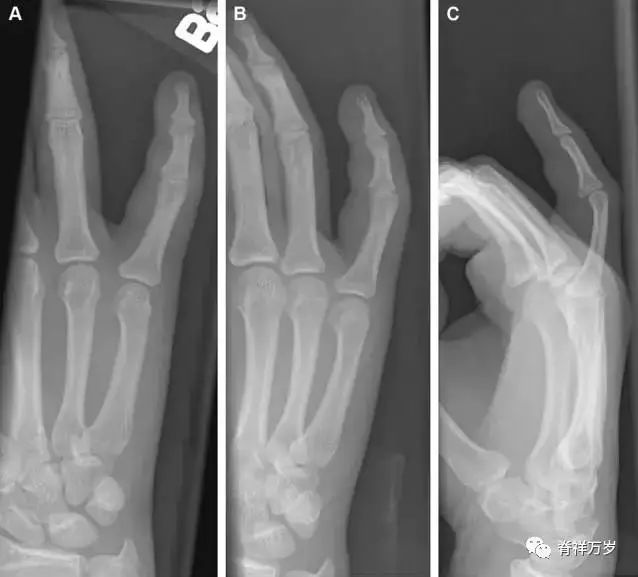

32.掌板骨折

掌板是掌指关节和指间关节关节囊掌侧的纤维结构,防止关节过伸。掌板的远端部是增厚的纤维软骨,附着于指骨掌侧基底部,而其两侧与侧副韧带的纤维融合。掌板骨折多发生于过伸损伤,为撕脱性骨折。

图 3 掌板骨折(A~C)小指前后位、斜位、侧位片,由于骨折的部位及特点,在前后位片上通常难以发现骨折;放大后的斜位(D)、侧位(E)可见一骨碎片(白色箭头)。